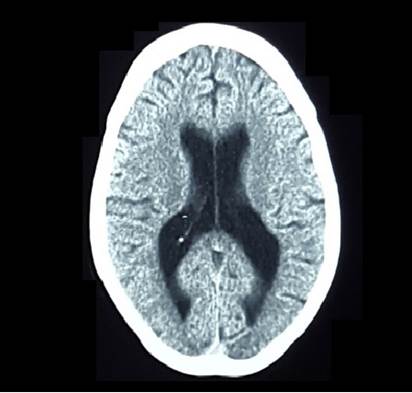

Tomografía (TC) cráneo (sin contraste): Sistema ventricular aumentado de tamaño a predominio supratentorial (Figura 3).No se pudo realizar RNM de cráneo.

En la TC de cráneo puede apreciarse atrofia generalizada, ventrículo megalia e hipodensidad de la sustancia blanca periventricular que realza con el medio de contraste 1,2,9,14,15, hallazgos presentes en el caso 3.

Aunque los hallazgos en la TC y RNM de cráneo poseen baja sensibilidad y especificidad para el diagnóstico de encefalitis a CMV, se han descripto imágenes que podrían sugerir la infección en un contexto clínico adecuado.